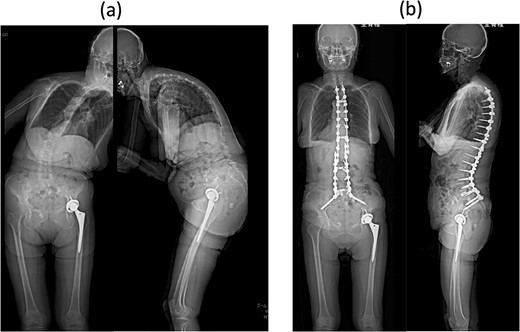

Proximal junctional kyphosis gradually developed after the initial surgery, eventually causing difficulty in maintaining a horizontal gaze 16 months post-surgery due to dropped head syndrome (Fig. 2a). A second corrective cervical spine surgery was performed 17 months post-surgery, involving extended fusion to C2 and pedicle subtraction osteotomy of T4 (Fig. 2b). The patient was extubated in the operating room immediately after the surgery and returned to the ward.

(a) Standing whole-spine radiographs 16 months after the first surgery, showing features of dropped head syndrome associated with proximal junctional failure; lateral radiographs immediately after (b) the second and (c) third surgeries; (d) standing whole-spine radiographs 16 months after the third surgery.

On postoperative Day 1, she resumed eating and drinking, but with delayed swallowing time. The wound drain was removed on postoperative Day 2, and walking exercises were initiated. Though no specific issues were noted, she exhibited signs of delirium, unclear responses, and occasional snoring-like breathing. However, on postoperative Day 6, a nurse found her bedridden, with a pale face and eyes open, drooling and snoring. The patient’s oxygen saturation was 55%; when the bed was flattened and the airway was suctioned, consciousness was restored and oxygenation improved in ~20 s. The diagnosis was obstructive dyspnea, supported by the persistence of snoring after resuming breathing. Neurological symptoms had not worsened, and intracranial lesions or cardiovascular events were deemed unlikely based on computed tomography (CT) scans, electrocardiograms, and blood test results. The rapid increase in the C2–7 angle from −15° before the second operation to 32° postoperatively led to the conclusion that a decrease in the O-C2 angle was associated with occlusive dyspnea. Emergency surgery was performed to re-fixate the cervical spine, reducing kyphosis (Fig. 2c). Postoperatively, the patient was managed on a ventilator and extubated on the second postoperative day. Sixteen months later, she experienced no further dyspnea (Fig. 2d and 3b).